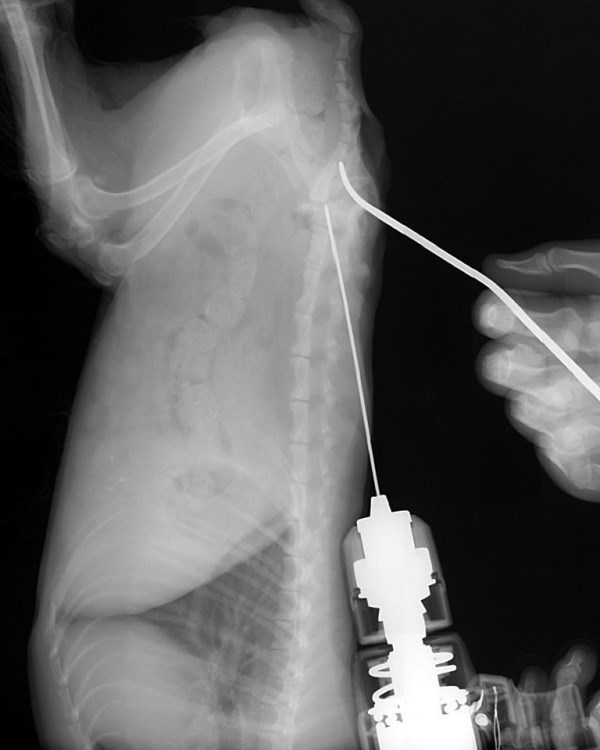

| Phẫu thuật đóng đinh với ca bệnh gãy xương chân ở chó (2019) |